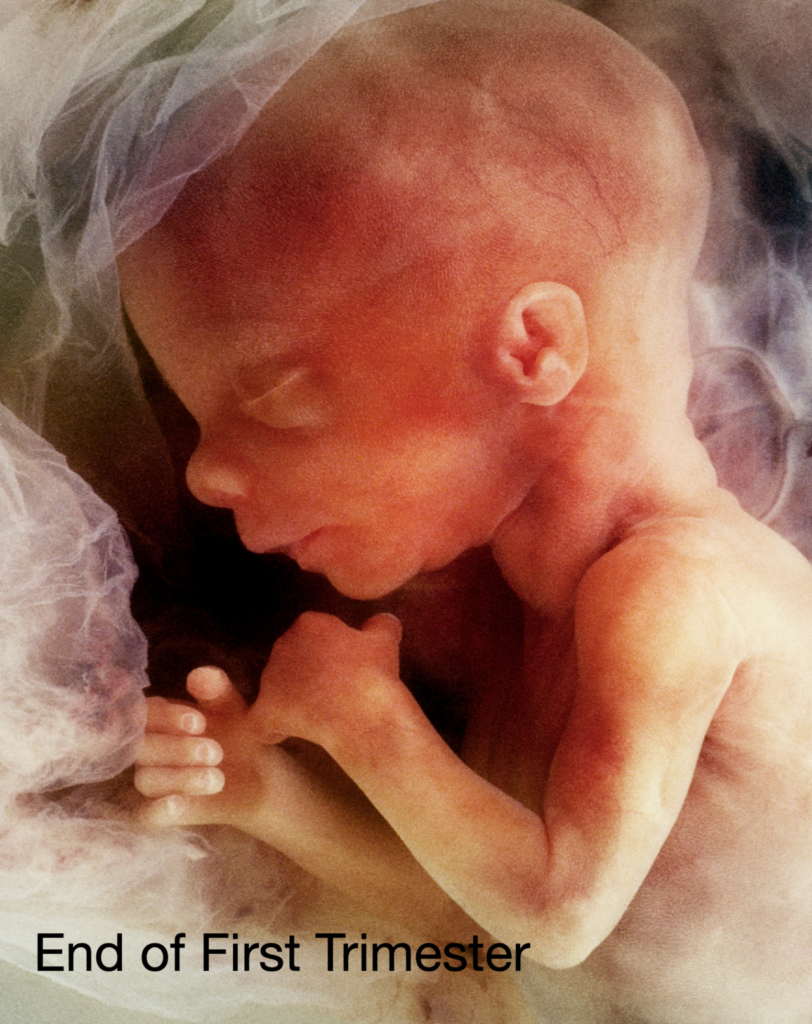

First Trimester: Embryonic Development

The first trimester of pregnancy is the most critical time for a developing baby. It spans from week 1 to week 12. During this time, the fertilized egg becomes a tiny embryo and quickly begins to grow and change.

Here are some of the most important milestones in the first trimester:

- Weeks 1–2: These are the weeks of fertilization and implantation. The fertilized egg travels down the fallopian tube and attaches to the uterus lining.

- Week 3: The zygote begins dividing and forms a tiny ball of cells. This is the beginning of embryogenesis.

- Week 4: The embryo forms a structure called the neural tube, which will become the brain and spinal cord.

- Week 5: The heart begins to form and will start to beat.

- Weeks 6–8: Major organs begin developing, including the lungs, stomach, and liver. Limb buds appear, which will become arms and legs.

- Weeks 9–12: The embryo becomes a fetus. Facial features become more defined, and tiny fingers and toes form.